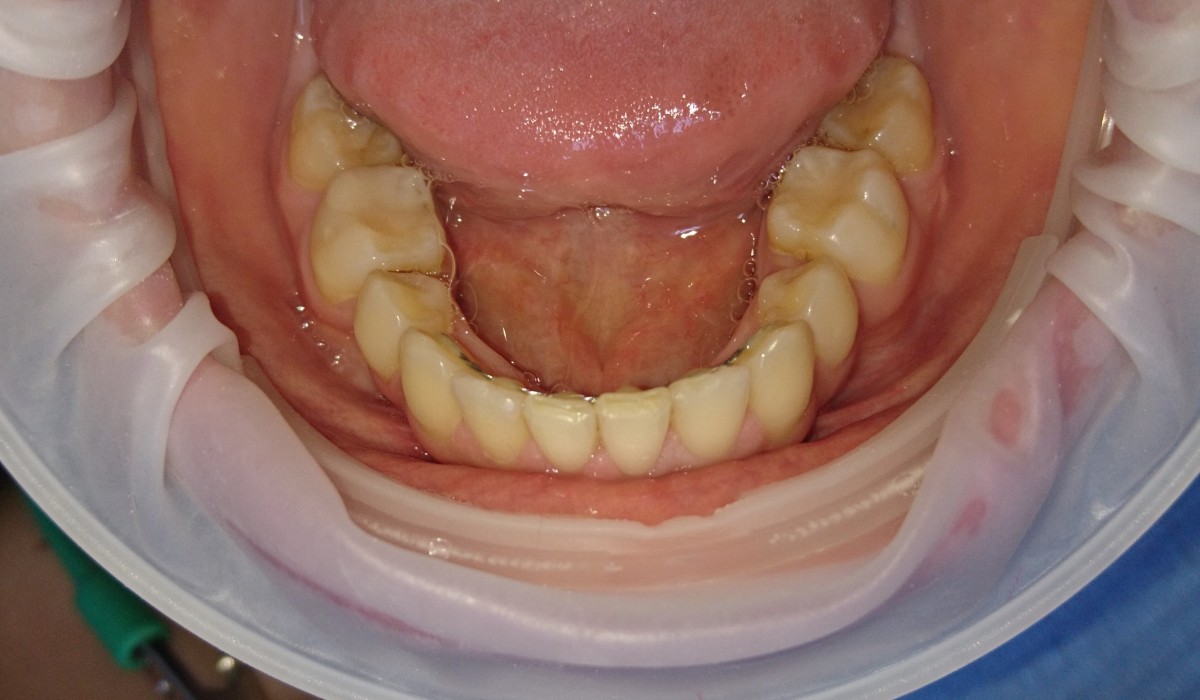

Pacient 23 ani. Extracție 1.4, 2.4, 3.5, 4.5, aparat ortodontic fix ceramic.